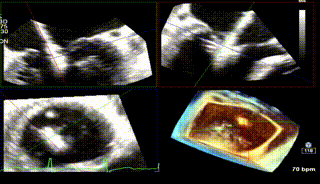

怎么上穿刺鞘攻克巨大左房伴转位穿刺难关!温医大附一院周浩教授团队创新应用“导丝定位+可调弯鞘”技术完成高难度TEER手术_https://www.jmylbn.com_新闻资讯_第2张

1区

怎么上穿刺鞘攻克巨大左房伴转位穿刺难关!温医大附一院周浩教授团队创新应用“导丝定位+可调弯鞘”技术完成高难度TEER手术_https://www.jmylbn.com_新闻资讯_第3张

1区带彩

怎么上穿刺鞘攻克巨大左房伴转位穿刺难关!温医大附一院周浩教授团队创新应用“导丝定位+可调弯鞘”技术完成高难度TEER手术_https://www.jmylbn.com_新闻资讯_第4张

2区

怎么上穿刺鞘攻克巨大左房伴转位穿刺难关!温医大附一院周浩教授团队创新应用“导丝定位+可调弯鞘”技术完成高难度TEER手术_https://www.jmylbn.com_新闻资讯_第5张

2区带彩

怎么上穿刺鞘攻克巨大左房伴转位穿刺难关!温医大附一院周浩教授团队创新应用“导丝定位+可调弯鞘”技术完成高难度TEER手术_https://www.jmylbn.com_新闻资讯_第6张

3区

怎么上穿刺鞘攻克巨大左房伴转位穿刺难关!温医大附一院周浩教授团队创新应用“导丝定位+可调弯鞘”技术完成高难度TEER手术_https://www.jmylbn.com_新闻资讯_第7张

3区带彩

怎么上穿刺鞘攻克巨大左房伴转位穿刺难关!温医大附一院周浩教授团队创新应用“导丝定位+可调弯鞘”技术完成高难度TEER手术_https://www.jmylbn.com_新闻资讯_第8张

3D

怎么上穿刺鞘攻克巨大左房伴转位穿刺难关!温医大附一院周浩教授团队创新应用“导丝定位+可调弯鞘”技术完成高难度TEER手术_https://www.jmylbn.com_新闻资讯_第9张

3D带彩

怎么上穿刺鞘攻克巨大左房伴转位穿刺难关!温医大附一院周浩教授团队创新应用“导丝定位+可调弯鞘”技术完成高难度TEER手术_https://www.jmylbn.com_新闻资讯_第10张

术前肺静脉频谱

怎么上穿刺鞘攻克巨大左房伴转位穿刺难关!温医大附一院周浩教授团队创新应用“导丝定位+可调弯鞘”技术完成高难度TEER手术_https://www.jmylbn.com_新闻资讯_第11张